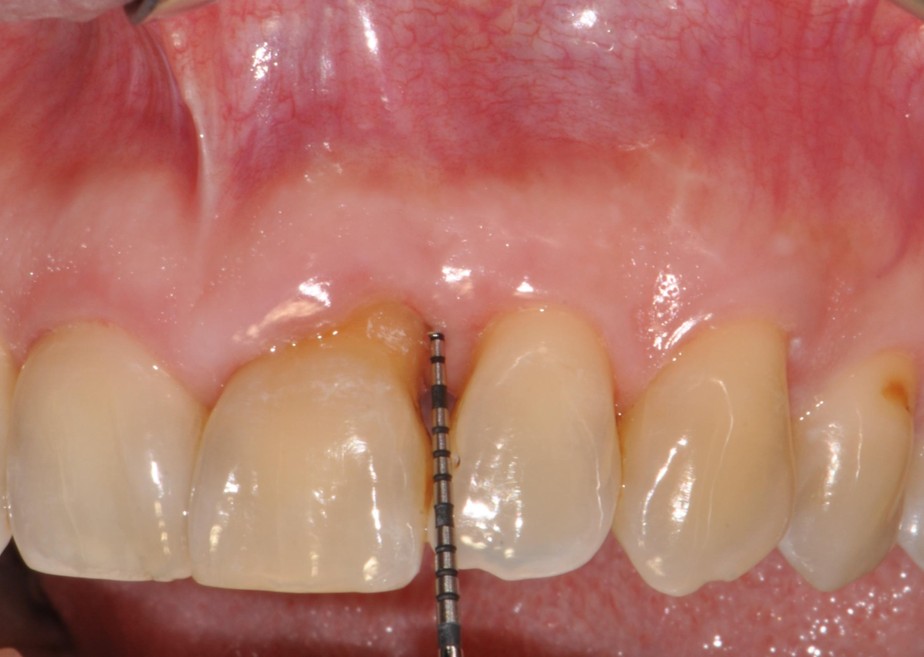

Nowadays, periodontal regenerative surgery has clearly demonstrated its ability to significantly improve the prognosis of teeth that were previously considered hopeless, particularly in the management of infrabony defects. Growing evidence further indicates that regenerative surgical approaches provide superior clinical outcomes compared with open flap debridement alone, not only in infrabony defects, but also in suprabony defects and furcation involvements.

Special attention will be given to incision design and flap management, with a strong focus on papilla preservation techniques as a key element in achieving wound stability and primary closure. Through a combination of evidence-based lectures and detailed clinical case discussions, participants will gain a comprehensive understanding of how to optimize regenerative outcomes in daily clinical practice.

The workshop will therefore highlight the importance of minimally invasive surgical concepts and appropriate biomaterial selection as critical factors in the successful management of advanced and complex periodontal defects. Ultimately, the aim of this workshop is to equip clinicians with practical tools and a structured clinical framework to apply regenerative concepts in a predictable manner, thereby maximizing long-term tooth retention and periodontal stability.